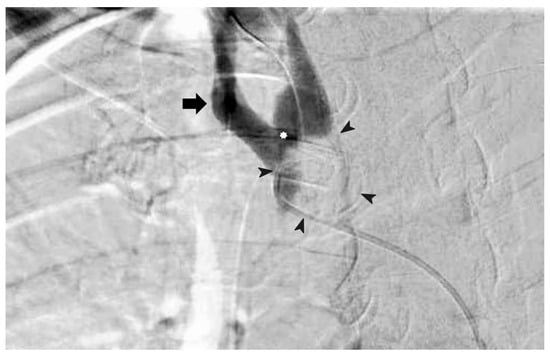

Over-Inflating a Tracheostomy Tube Cuff for Tracheo-Innominate Artery Fistula